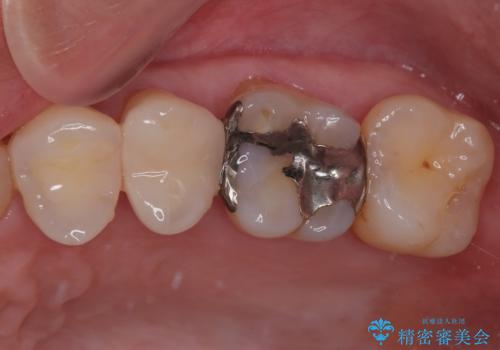

特に異常もなく見た目、噛み合わせともに満足していただけました。

ラバーダム防湿を行い、セラミックの接着をすることで、唾液や血液などの接着阻害因子を排除することができます。

歯と歯の間の虫歯をコンポジットレジンや保険のメタルインレーで治すと段差ができたりして清掃性が悪くなるので、セラミックインレー修復やゴールドインレー修復などの適合の良い詰め物で治療することをオススメします。